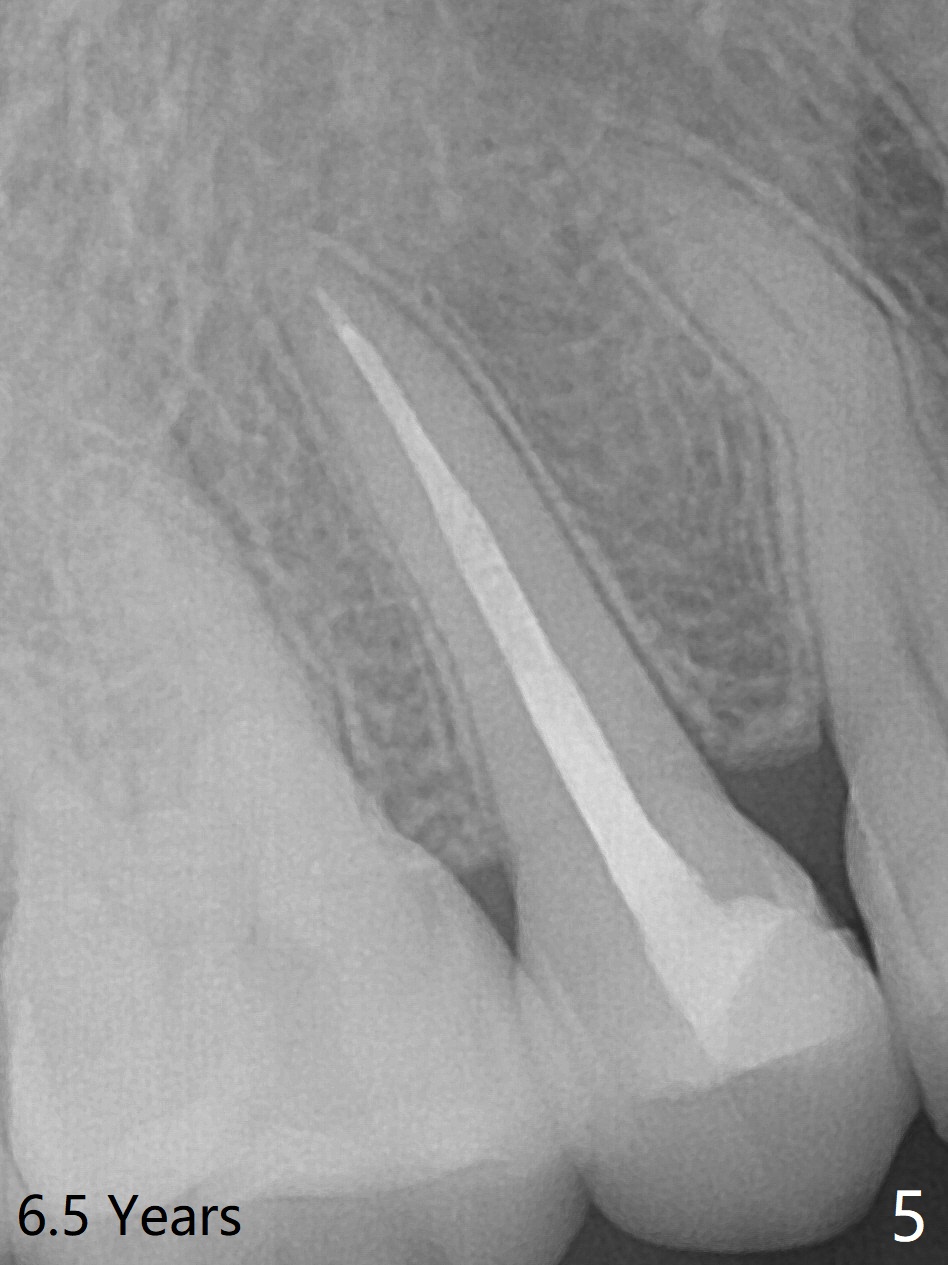

A 29-year-old woman presented to office with multiple amalgam restoration 7 years ago. The tooth #4 developed acute pulpitis 7 months later (Fig.2). The tooth has 2 fused canals; after RCT, composite was placed; after discussion, the patient chose no crown (Fig.3). There is no recurrent periapical radiolucency or tooth fracture 2.5 (Fig.4) or 6.5 (Fig.5,6) years postop.